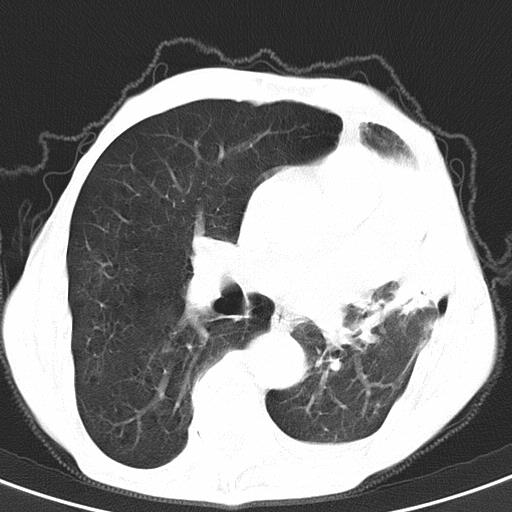

患者78岁,咳嗽胸闷一年余,近月来左侧胸痛;

建议强化,首先考虑左肺癌胸膜转移。

左侧少量胸腔积液,局限胸膜增厚,结合病史,考虑慢性肺炎.

患者左侧胸廓塌陷说明是长期病变,考虑tb性胸膜炎可能性大,另外有明显的肺气肿,建议行结核菌素实验,或者增强扫描

1.慢支肺气肿。2.左肺感染,建议治疗后复查。3.左侧少量胸水。

1.慢支肺气肿。2.左肺感染,建议治疗后复查,待除外继发性肺结核合并感染。3.左侧少量胸水。

1)考虑左肺慢性感染性病变(结核可能)。2)左肺上叶周围型肺癌不排除;建议追踪复查。3)肺气肿。4)左侧胸腔积液,左侧胸膜增厚、粘连。